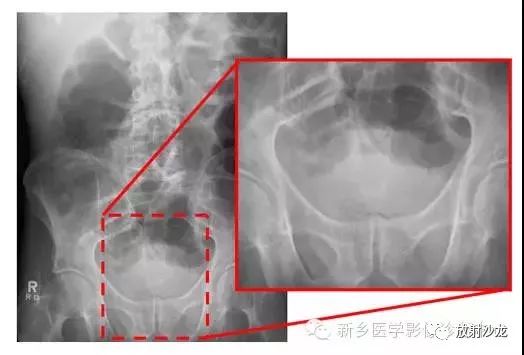

腹痛患者的腹部X光片水平位(左侧)和直立位(右侧)所上图示。是什么原因导致该病人的不适呢?

X线片表现出充满整个腹部的乙状结肠扭转。乙状结肠的两端可以理解成一个倒置的朝向骨盆的U型(图U)。在X光片直立位,可以看出气液平面(箭头)。咖啡豆的标志是乙状结肠扭转的典型的表现。充满气体的肠道包绕重叠水肿的肠壁所形成致密的白线,类似于一个咖啡豆。在这些X光片中,大肠的其余部分均不膨大,大概是因为扭转的点不造成阻塞,从而使消化产物可进入乙状结肠。

逆行通过肛管后所行X光片所示,证明了乙状结肠襻和正常肠道结构压力减低。